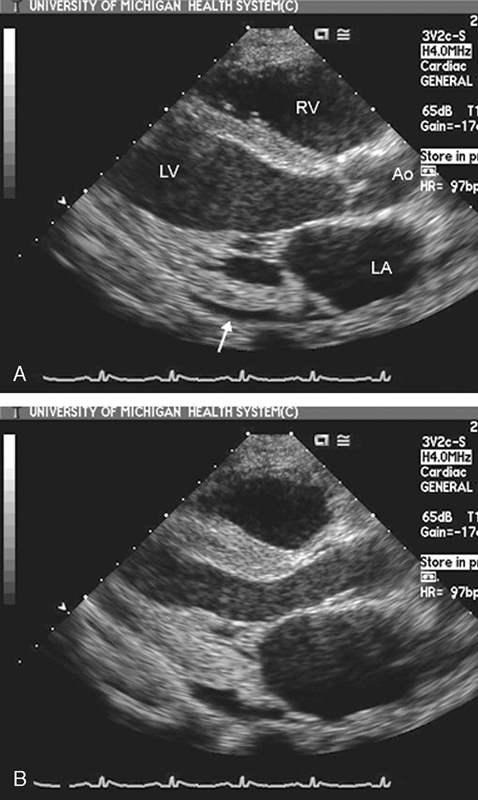

فحوصات تشخيصية لبعض امراض القلب والشرايين التاجية